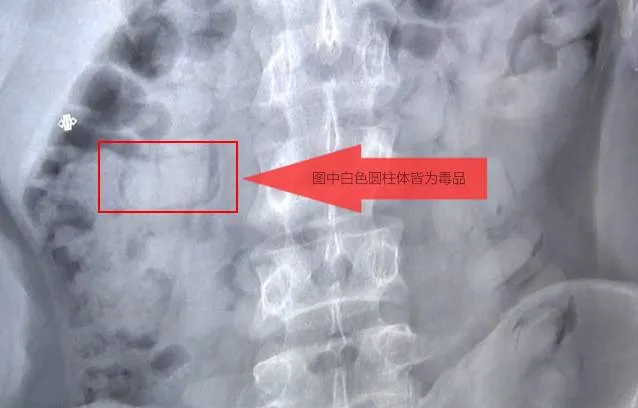

民警将王某带至医院进行了DR检查,通过 DR检查发现腹内有大量异物后,王某供述了其受境外一男子安排,在“金三角”地区吞服了70粒使用塑料袋、透明胶带等物品包装的海洛因,将毒品运至烟台交货的犯罪事实。